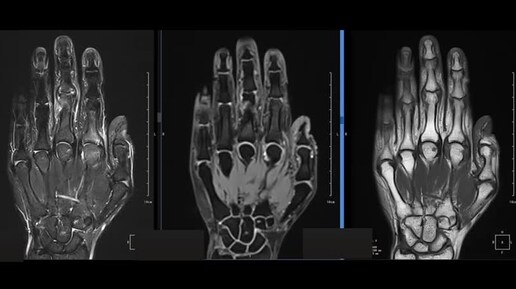

МРТ кисти